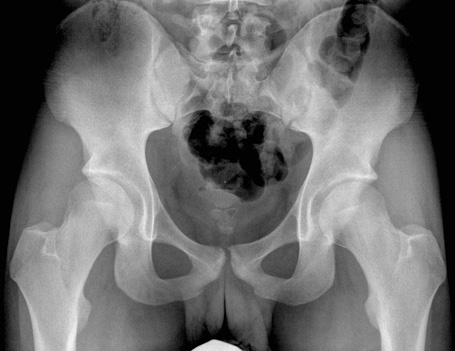

Anterior Inferior Iliac Spine

Anterior Superior Iliac Spine

Femoral Head

Femoral Neck

Femur

Greater Trochanter

Iliac Crest

Inferior Pubic Ramus

Ischial Ramus

Ischial Spine

Lesser Trochanter

Obturator Foramen

Pubic Symphasis

Sacrum

Superior Pubic Ramus